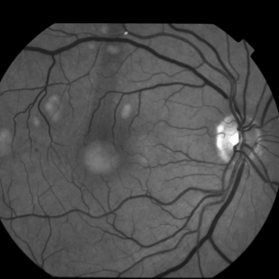

This 68 year old man was referred with a maculopathy but with normal visual acuity. He is thought to have multifocal Best Disease; there is no evidence of inflammation or uveitis and no history of cancer. Macular exam reveals yellow subretinal pigment clumping in each macula, including the foveal area. OCT shows moderate hyper-reflective PED, with no evidence of subretinal fluid or macular edema. Angiography reveals blocking defects due to pigment clumping with no evidence of CNVM.

Multifocal Best Disease Multifocal Best DiseaseJan 31 2015 by Thomas A. Ciulla, MD, MBA, FASRS Macular exam reveals yellow subretinal pigment clumping in each macula, including the foveal area. Photographer: Charlotte Harris Condition/keywords: adult vitelliform dystrophy, Best disease